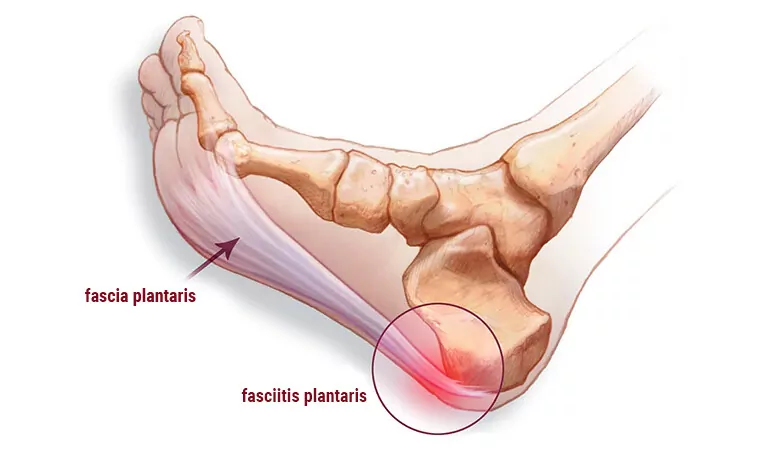

- Bei der Tendinopathie handelt es sich um eine Sehnenentzündung und degenerative Veränderungen in der Sehne, einschließlich Tendinitis (akute Entzündung der Sehne). Eine Tendinopathie ist ein lang anhaltender oder chronischer Zustand, der mit strukturellen Veränderungen der Sehne einhergeht und nicht unbedingt mit einer akuten Entzündung verbunden ist. Eine Tendinopathie kann sich durch die Chronizität einer Tendinitis oder durch eine allmähliche Degeneration der Sehnenstruktur entwickeln.